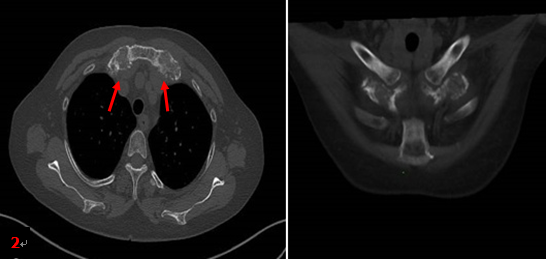

患者同期胸部CT檢查所見(圖2箭):雙側第1前肋對稱性肥厚、膨大、骨質硬化,未見明顯軟組織腫塊。